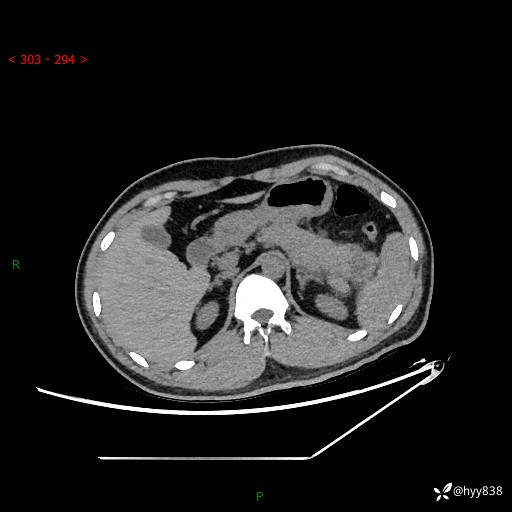

【患者信息】:31岁/男

【主诉】:间断性左下腹疼痛10天

【现病史及既往史】: 患者10余天前无明显诱因出现左下腹部疼痛,呈间断性,无恶心,呕吐,无黄疸,腹泻症状,于当地医院就诊,行腹部C提示:胰腺尾部占位。2型糖尿病。现患者为求手术治疗,门诊以“胰腺肿物”收入院。 患者起病来,一般情况可,大小便正常,体重体力未见明显减轻。

【检查】:胰腺CT平扫+增强